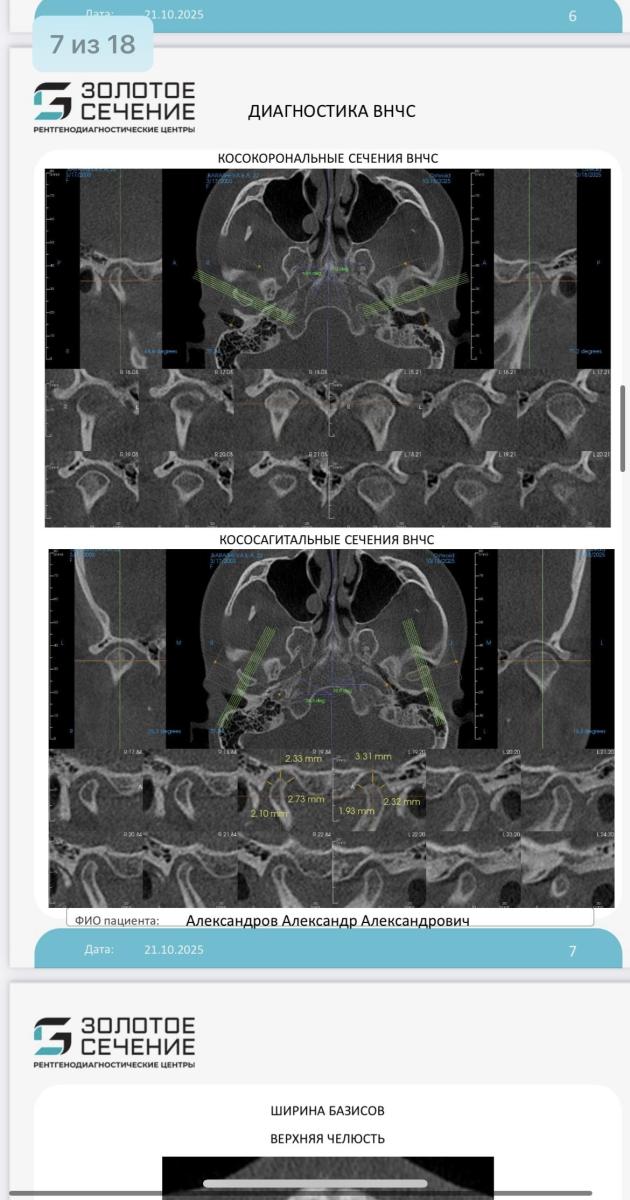

У меня открытый прикус, в детской стоматологии мне сказали делать только операцию

Сейчас уже прохожу во взрослой клинике обследование и тоже самое говорят, брекеты при открытом прикусе не помогут только члх